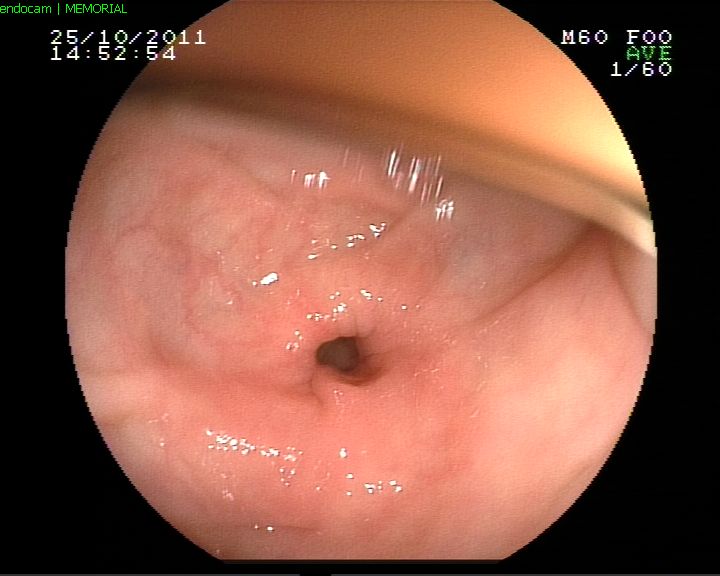

Mide ülseri

Onikiparmak barsak ülseri